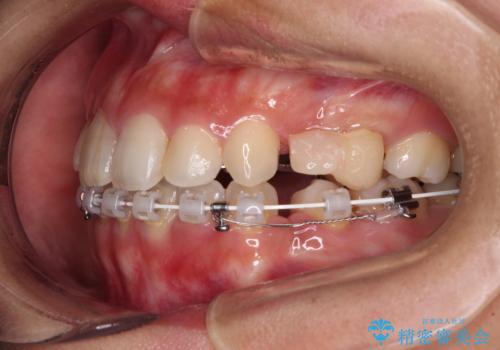

- ハーフリンガル

- 八重歯や前歯のデコボコを気にして来院された患者様です。

目立たない装置を希望されたので、上顎が裏側装置のハーフリンガルを選択し、上下左右の小臼歯(計4歯)を抜歯して矯正治療を行うこととしました。

補助装置を併用することで、八重歯を速やかに改善し、治療期間の短縮を図ることとしました。

裏側装置での矯正治療は、上顎前歯の正中のズレをまっすぐに改善することが難しいのですが、きれいに整えることができました。

補助装置を用いて抜歯したスペースを速やかに閉じたことで、短期間での治療となりました。